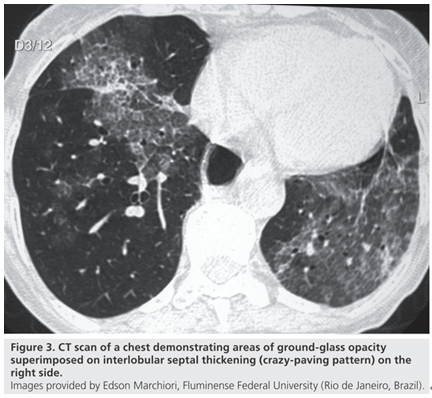

脂质性肺炎被认为由肺泡内含脂物质异物反应所致,脂质到达肺泡的机制:摄入(非挥发烃类)或吸入(挥发烃类),少数矿物油如汽油,即使经静脉注射也可导致肺损伤。在肺泡内,油脂乳化后被巨噬细胞吞噬,肺泡巨噬细胞不能代谢脂肪物质,当巨噬细胞死亡后油脂反复进入肺泡;油脂异常释放导致巨噬细胞肉芽肿反应、慢性炎症反应、肺泡及间隔纤维化;新鲜病灶显示肺泡被载脂巨噬细胞浸润,肺泡壁和间隔基本正常;进展性病灶显示巨大的空泡和肺泡壁、支气管壁和间隔炎性浸润,大量含脂空泡周围纤维化和实质破坏是晚期病变的特征。如果吸入矿物油或植物油,不易在体内分解,易在体内形成结节或肿块。如果吸入动物油,在体内可被分解为脂肪酸,导致炎症反应,局部肺水肿或肺出血。临床表现缺乏特异性,个体差异明显,从无症状到严重,甚至危及生命,常因患者年龄、吸入脂质的时间、数量及种类而不同。有症状的外源性脂质性肺炎常表现为慢性咳嗽或呼吸困难,其他表现为胸痛、咯血、间歇发热等。查体可发现叩诊浊音,听诊可闻及爆破音或干啰音。在长期持续进展性疾病患者中,体检可发现慢性缺氧,如杵状指。外源性类脂性肺炎可模拟许多其他肺部疾病,包括癌、肺炎、急性呼吸窘迫综合征和局部肉芽肿,HRCT最常见的表现是气腔实变、磨玻璃影、铺路石征、小叶间隔增厚、肿块样病变。急性外源性脂质性肺炎一般在吸入后半小时内出现肺部影像异常,大部分患者在24小时内出现肺部阴影,通常呈磨玻璃或实变影,一般在2周至8个月可逐渐改善或吸收,偶尔会遗留少许瘢痕纤维。慢性外源性脂质性肺炎最常见的影像学表现为一个或多个肺段的磨玻璃结节或实变影,通常在支气管周围分布,累及下叶最常见。实变可伴临近肺组织扭曲,在疾病晚期,由于油脂从肺泡内运送至肺间质,可出现增厚的小叶间隔或纤维化,还可见到铺路石征,也可表现为含脂质的结节或肿块影,由于慢性炎症及纤维化,肿块边界常不规则或有毛刺。下图为文献报道的一例急性外源性脂质性肺炎,患者胸部CT主要表现为实变,其中有液化坏死灶。下图为3例外源性脂质性肺炎患者的胸部CT,主要表现为肺结节/肿块和磨玻璃影。治疗3个月后,病变较轻者明显吸收。外源性脂质性肺炎的诊断主要基于暴露史,与疾病相符的影像学改变,唾液、支气管肺泡灌洗液或活检肺组织病理发现富含脂质的巨噬细胞,需要综合以上考虑诊断。支气管肺泡灌洗液的外观有提示价值,常为白色或浑浊液体,在表面可见脂肪漂浮层。